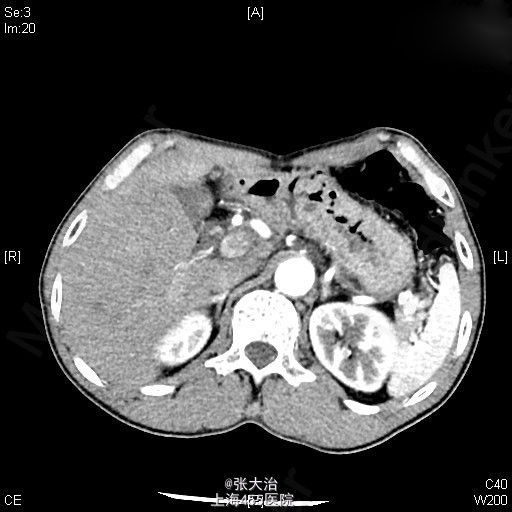

查体:神志清晰,精神尚可,呼吸平稳,营养中等,表情自如,发育正常,自主体位,应答流畅,查体合作。全身皮肤无黄染,无肝掌、蜘蛛痣。全身浅表淋巴结无肿大,无明显贫血貌,左锁骨上淋巴结(-);腹部平坦,未见肠型或胃蠕动波,未见腹壁静脉曲张;全腹软,无压痛、反跳痛、肌紧张。肝脾肋下未及,包块未及;移动性浊音(-),肠鸣音正常,每分钟约3次,不伴高调音、气过水声。 2014-4-10某人民医院就B超(92301):肝囊肿,左肝内胆管扩张;MRI(1697647):肝门区病变可能伴左肝内胆管扩张。 2014-4-22某人民医院MRCP(68941):肝门处占位伴肝内胆管扩张,考虑胆管细胞癌可能大,肝多发囊肿。 肝动脉CTA、门脉CTV、肝静脉CTV、下腔静脉CTVCT【2014-05-05 我院】 :肝门区MT,肝左、右动脉及门脉主干、左支受侵;肝及双肾小囊肿。 上腹部平扫+增强+DWI+MRCPMRI【2014-05-06 我院】 :肝左叶MT(胆管细胞型机会大)伴肝左叶胆管扩张,门脉受侵;肝、双肾小囊肿。 肝脾及门脉;胆(含胆总管);肾+输尿管;胰超声【2014-05-05 我院】 :超声造影:肝门部偏左侧实质占位--考虑肝门部胆管MT,侵犯门脉左支可能;肝左叶胆管扩张;右肾囊肿 肝脏超声造影超声【2014-05-05 我院】 :超声造影:肝门部偏左侧实质占位--考虑肝门部胆管MT,侵犯门脉左支可能;肝左叶胆管扩张;右肾囊肿 肝脏术后(检查胸水、腹水、手术区、膈下)超声【2014-05-20 我院】 :右侧胸腔少量积液;腹水